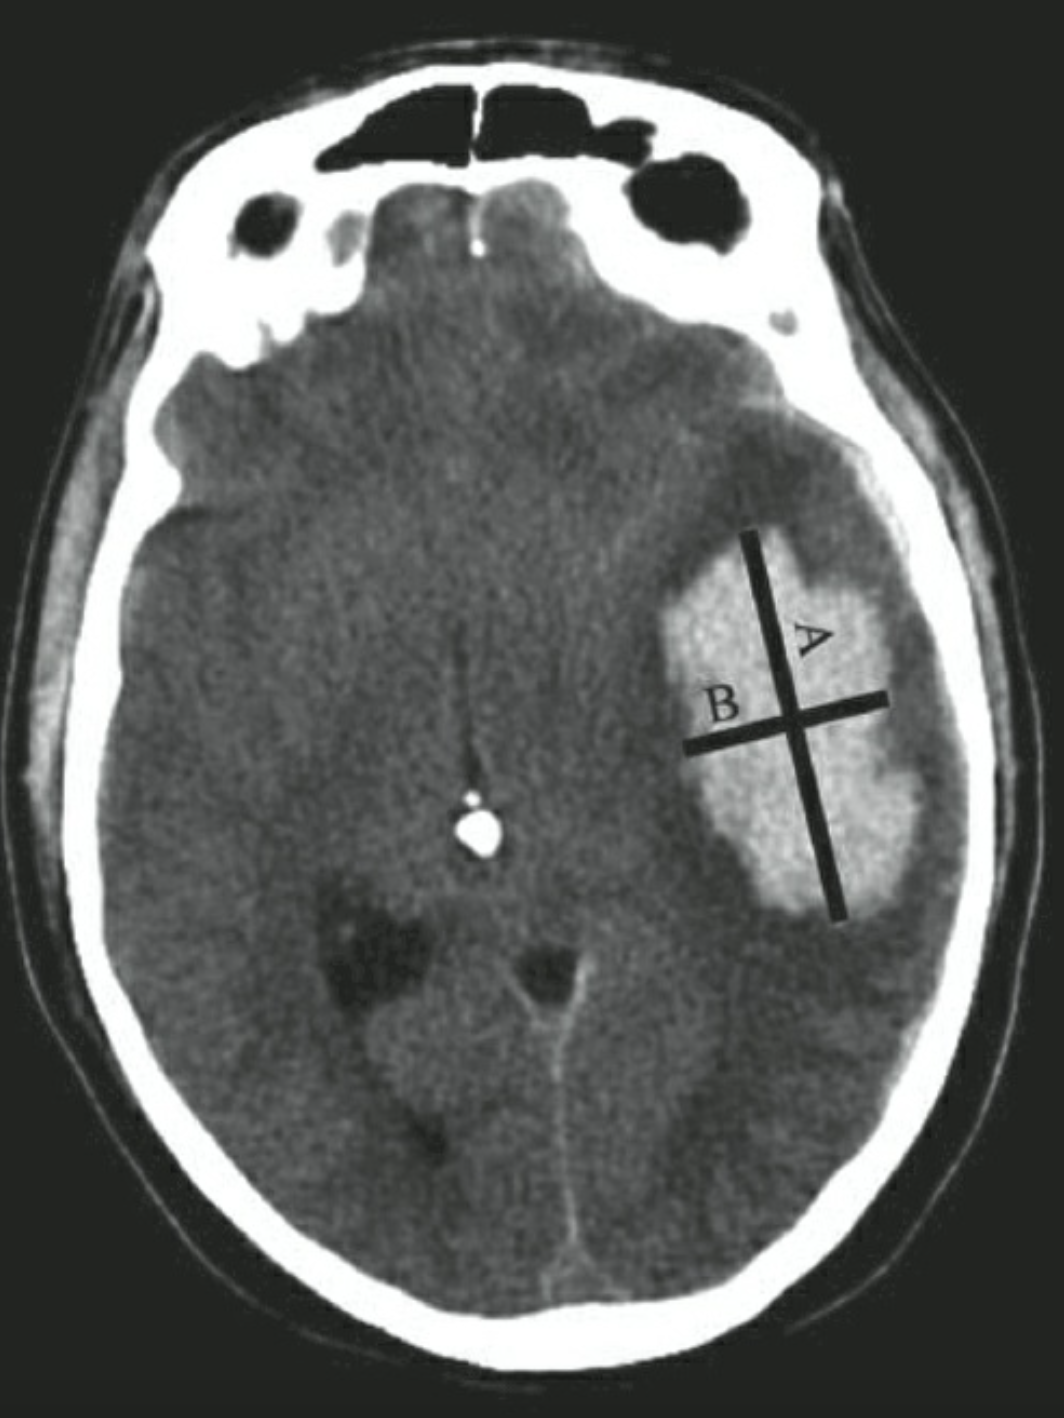

Tính thể tích khối máu tụ (mL) = (A x B x C x 0,5 cm) / 2